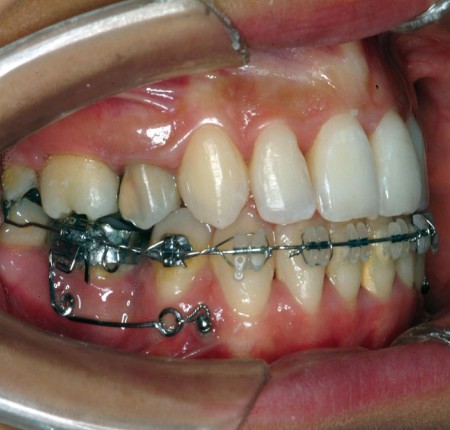

En ancrage indirect, la mini-vis peut être solidarisée à une dent par un arc acier de grosse section, afin d’utiliser cette dernière comme ancrage strict (Fig. 12a). Ce système permet alors de garder une réflexion biomécanique conventionnelle en appliquant une force motrice qui reste dans le plan de l’arc, de la dent ancrée à la molaire à mésialer. Elle procure de plus un plus grand confort au patient, mais les conséquences biologiques de la diminution de la mobilité physiologique de la dent ancrée sont à prendre en considération, même s’il n’existe pas d’article permettant d’incriminer ce système biomécanique à ce sujet. De plus, il est à noter que cette configuration indirecte n’écarte pas le risque de l’effet parasite dû à l’arc-boutement précédemment décrit, si la traction est appliquée entre la prémolaire d’ancrage et la molaire (Fig. 12b), avec un risque de vestibulo-version des incisives. Une solution consisterait à ajouter un stop en distal de la 5, afin d’empêcher l’arc de glisser au travers de son attache et ainsi d’éviter ce risque dans cette configuration.

Figure 13 : (a) schématisation des forces en présence lors d’une mésialisation molaire avec ancrage indirecte par ligature (b) Schématisation des effets parasites

Le choix du site de pose de la mini-vis est une étape importante, même dans son utilisation indirecte. Les sites couramment utilisés sont entre 3-4 et 4-5. En ancrage indirect, l’implantation peut aussi se faire entre 2-3 si l’un de ces sites ne peut être choisi à cause d’un obstacle anatomique (frein latéral, trou mentonnier, proximité radiculaire). Ce site, en raison de sa situation plus antérieure est contre-indiqué en utilisation directe pour des raisons pratiques (la chaînette serait alors plaquée contre la gencive attachée) et biomécaniques (la force motrice contiendrait une composante de contraction de l’arcade).

Pour une telle utilisation de la mini-vis (Fig. 13), nous recommandons une implantation antérieure, entre 3-4. En effet, une implantation entre 4-5 augmente la composante verticale de la ligature et, ainsi, son angle par rapport à la ligne directe entre la mini-vis d’ancrage et la molaire. La prémolaire d’ancrage se voit alors autoriser un certain degré de version suivant l’arc de cercle centré sur la mini-vis avec le rayon représenté par la ligature métallique. Cliniquement, un diastème pourrait apparaître en mésial de la dent ligaturée.

La mini-vis peut aussi être directement ligaturée à l’arc par l’utilisation d’un crochet serti sur ce dernier. Dans ce cas de figure, la force de traction se doit d’être appliquée sur l’arc lui-même, afin d’éviter le mouvement distal le long de l’arc de la prémolaire d’ancrage. Dans cette configuration, on peut alors avoir recours à un stop serti en distal de cette dernière.